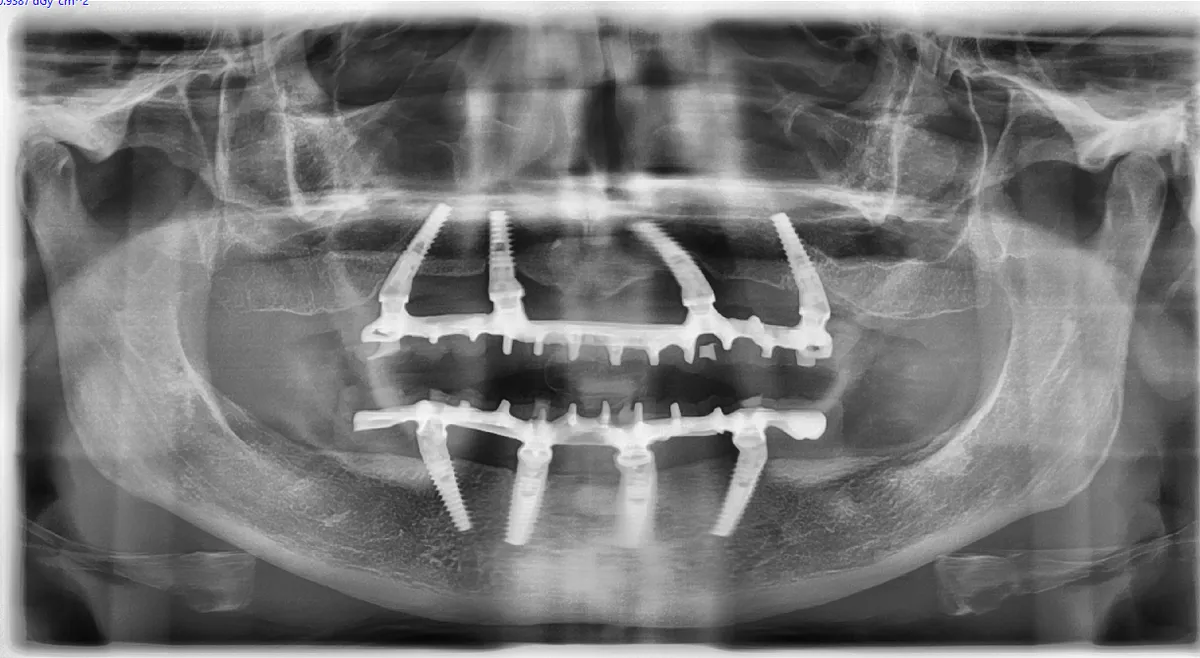

Le testate nazionali rilanciano il corso Espansione Osteo-Mucosa 4.0 tenuto a Bologna. Un team di Frosinone porta le tecniche rigenerative in Italia.

Corso Espansione Osteo-Mucosa 4.0 a Frosinone, 15 marzo 2025. Tecnica di split crest per odontoiatri. Resoconto della giornata.

Resoconto della VI Edizione dell'incontro Amici di Ca' Fondi a Soriano nel Cimino. Tessuti molli, espansione ossea e lo spirito giusto.

Relazione al primo Congresso Nazionale SIOD a Palermo su espansione verticale e orizzontale agevolata e gestione dei tessuti molli.